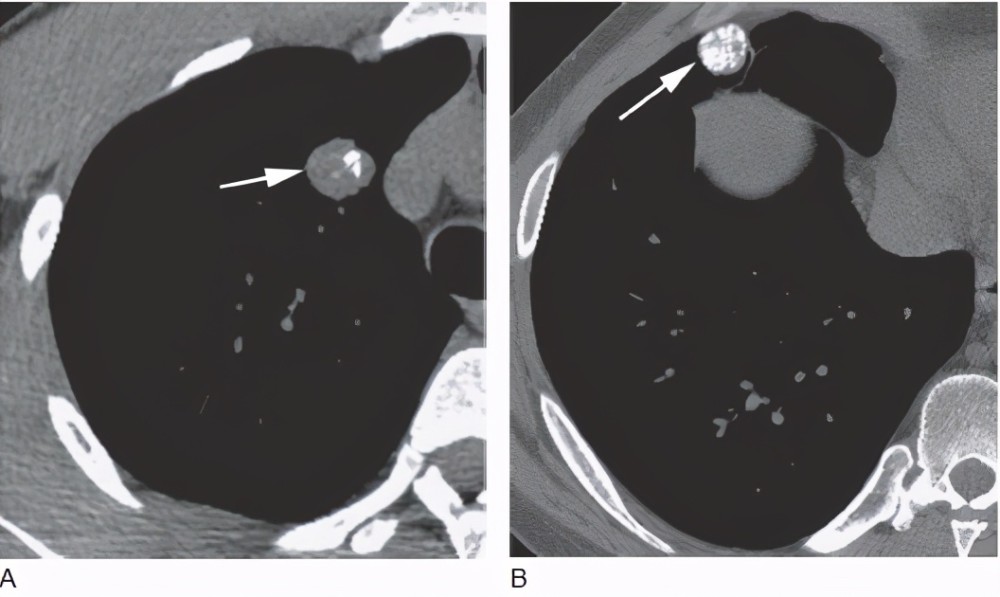

3.结节样钙化灶

胸片和或CT报告中常提示结节样钙化灶或者钙化结节之类的描述 , 这个也是不必担心的 。 肺部钙化结节是疾病恢复后遗留的一种疤痕 , 大多数由于既往的肺结核或肺炎所致 , 尤其是两上的肺的钙化灶绝大多数与既往肺结核感染相关 , 有时候影像科医生会直接写上 , 考虑陈旧性肺结核 。 这类钙化灶或钙化结节会长期存在不变化 , 小范围的钙化结节灶对肺功能没有任何影响 。